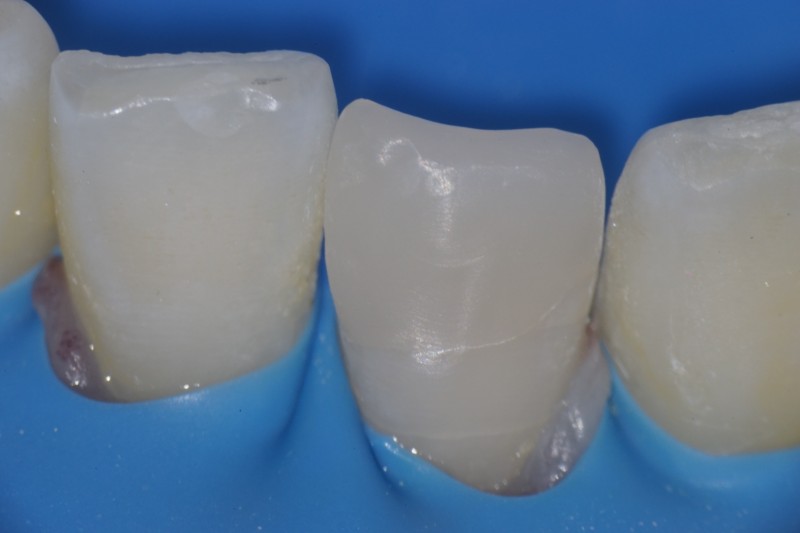

その上をダイレクトボンディングで修復しました。

ラバーダムを外して完成です。

神経を保存して、詰め物で修復することにより、極めて低侵襲な治療をすることができました。